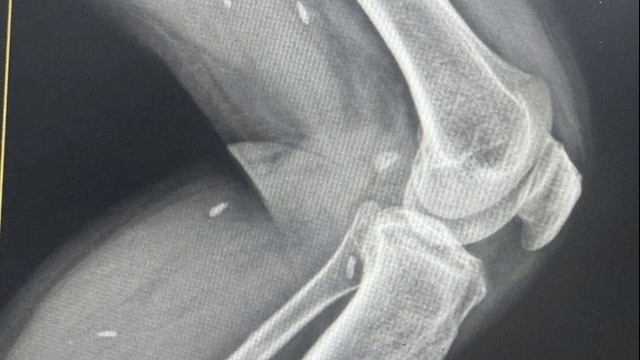

![]() |

| Nhóm "Bông hồng đen" tại buổi làm việc với UBND phường Hải Sơn (Ảnh: Tuyên giáo quận Đồ Sơn) |